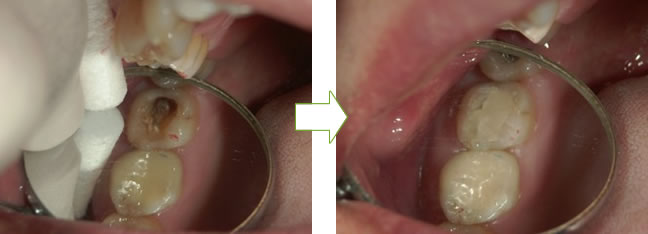

befor after

befor → ドックベストセメントを入れる → after